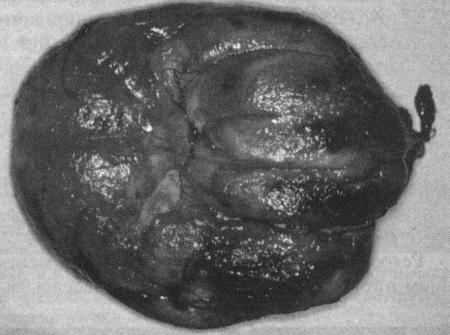

ГЛАВА 3

Бесплодие самок

П. Райт, Д. Уоттс (Patric J. Wright and John R. Watts)

Нарушения, характеризующиеся отсутствием эструса

Анэстрия может проявиться следующим образом: либо у самки в соответствующем возрасте не началась циклическая активность, либо увеличена продолжительность интер-про-эструса (т. е. более 12 месяцев для сук и более 20 дней для кошек), либо прекратилась циклическая активность. Патология обусловливается отсутствием явных признаков проэструса и эструса или структурными либо функциональными нарушениями в системе гипоталамус-гипофиз-яичники.